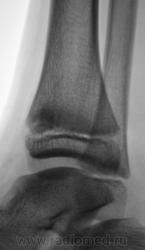

Травма. Пациент направлен хирургом на рентгенографию голеностопного сустава. Произведено стандартное исследование.

Уважаемый Валентин Львович! А что в жалобах, анамнезе? В переднемедиальной зоне дист. метафиза б/берцовой кости субхондрально под зоной роста участок уплотнения к/структуры, не отграниченный от неизмененной костн. ткани. Возможно, это импрессионный перелом? или остеонекроз? Смущает небольшой очаг аналогичной структуры в таранной кости под медиальным валом блока.

Согласен с коллегой helenmar по поводу перелома по типу импрессии, а ещё подвывих стопы в г/стопном суставе.

А как же объяснить асимметрию рентгеновской суставной щели?

А на мой взгляд, суставная щель вполне симметрична.

У взрослого такие соотношения в суставе назову супинационным подвывихом, хотя прямая проекция не оптимальна для такого заключения, боковая вовсе косая.